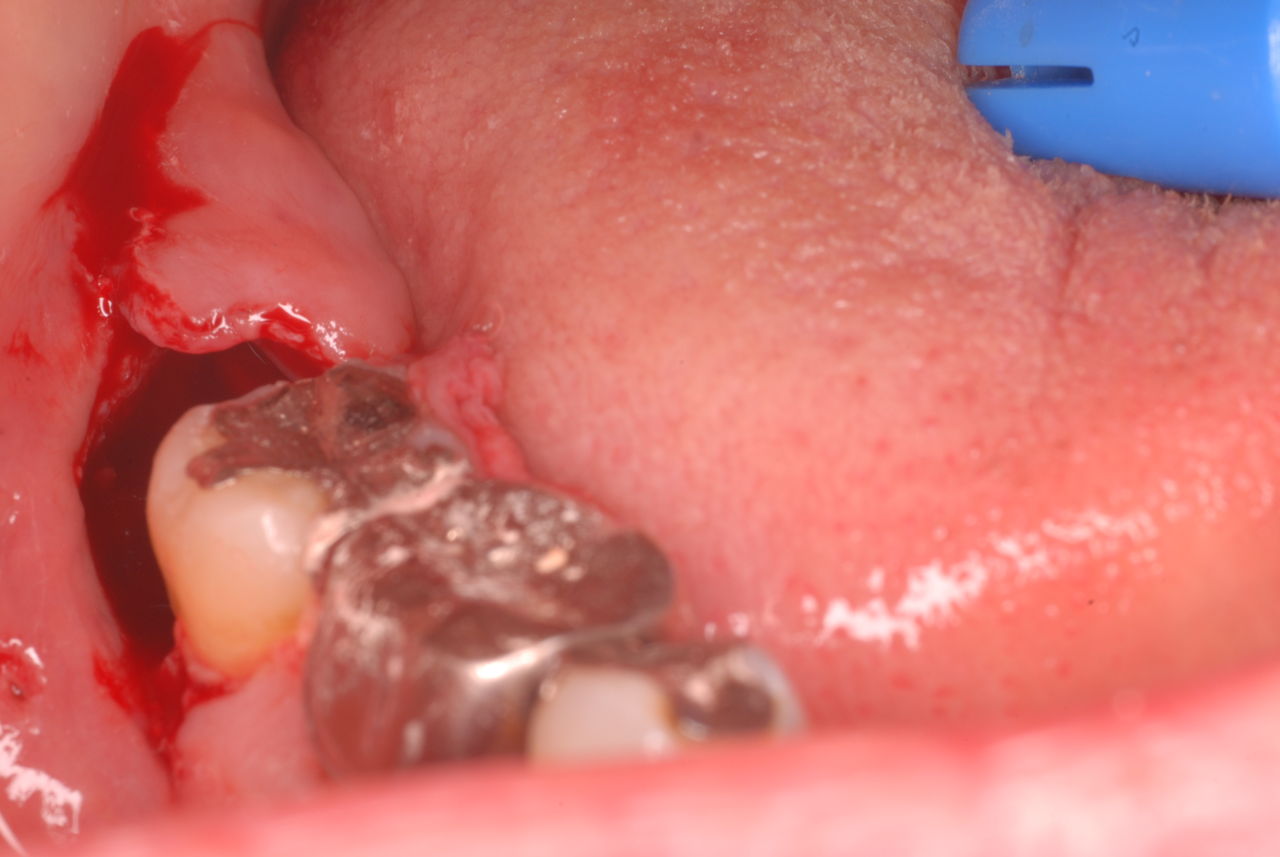

左下の歯は歯の中の治療も?ですごい歯周病を患い歯茎の穴(ポケットと呼ばれるところ)から膿が出ているのです。ばい菌と毒素で骨が溶けて深い穴ができてそこにまたバイキンと毒素がたまるという悪循環ができているのですね。